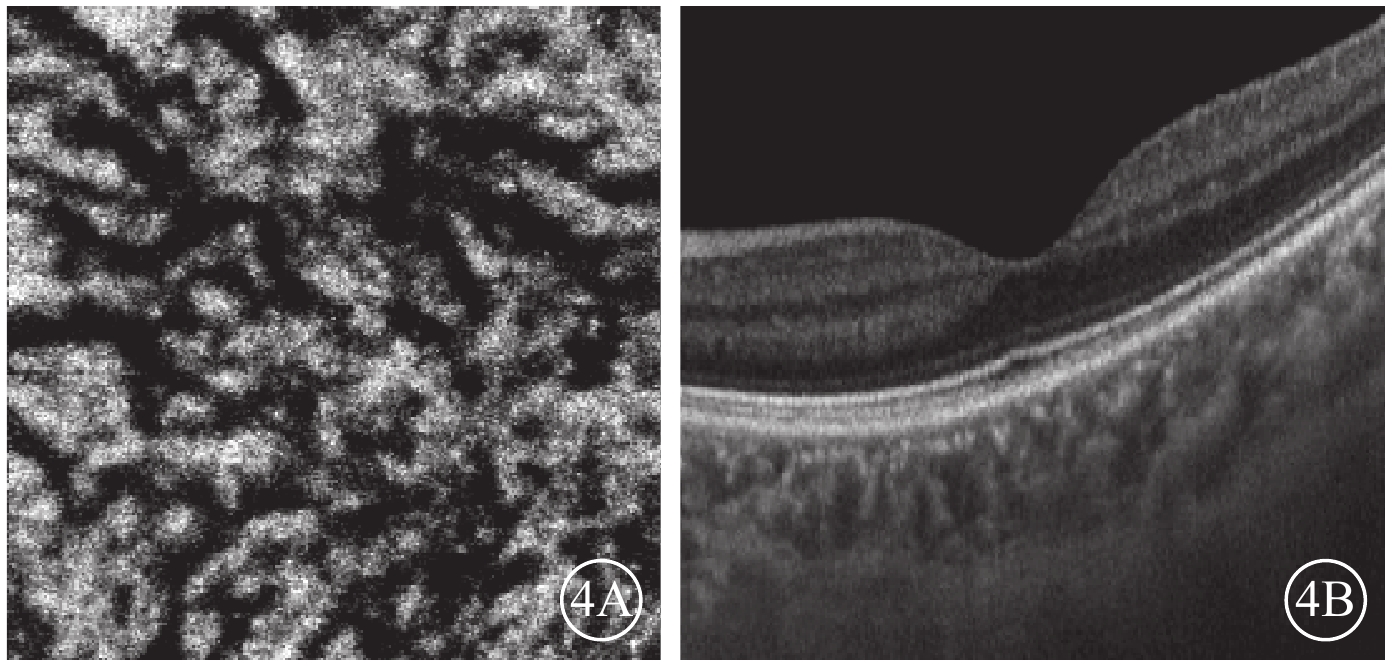

Bruch膜下1/2脈絡膜厚度層面,SS-OCTA圖像呈現與平面(en-face)OCT所示脈絡膜大血管分布較為一致的黑色血流信號,經二值化處理后所得的黑白圖像能反映脈絡膜大血管層的高速血流分布(圖2)。ECS組受檢眼脈絡膜SS-OCT和脈絡膜大血管層SS-OCTA表現為個別脈絡膜大血管極度擴張、高速血流匯聚和脈絡膜大血管普遍擴張、高速血流彌漫分布兩種類型。13只眼中,個別脈絡膜大血管極度擴張、高速血流匯聚6只眼;脈絡膜大血管普遍擴張、高速血流彌漫分布7只眼(圖3),其中1只眼為漿液性脈絡膜視網膜病變。對照組受檢眼脈絡膜SS-OCT無明顯大血管擴張征象,脈絡膜大血管層SS-OCTA圖像顯示高速血流分散而細小(圖4)。ECS組、對照組受檢眼脈絡膜大血管層FBFD分別為(76.35±14.46)%、(63.57±13.42)%;兩組受檢眼脈絡膜大血管層FBFD比較,差異有統計學意義(t=2.775,P=0.01)。

圖4

對照組脈絡膜大血管層en-face SS-OCTA和B掃描圖。4A. en-face SS-OCTA,高速血流分散稀少;4B. B掃描圖,脈絡膜大血管無明顯擴張

圖4

對照組脈絡膜大血管層en-face SS-OCTA和B掃描圖。4A. en-face SS-OCTA,高速血流分散稀少;4B. B掃描圖,脈絡膜大血管無明顯擴張

Bruch膜下1/2脈絡膜厚度層面,SS-OCTA圖像呈現與平面(en-face)OCT所示脈絡膜大血管分布較為一致的黑色血流信號,經二值化處理后所得的黑白圖像能反映脈絡膜大血管層的高速血流分布(圖2)。ECS組受檢眼脈絡膜SS-OCT和脈絡膜大血管層SS-OCTA表現為個別脈絡膜大血管極度擴張、高速血流匯聚和脈絡膜大血管普遍擴張、高速血流彌漫分布兩種類型。13只眼中,個別脈絡膜大血管極度擴張、高速血流匯聚6只眼;脈絡膜大血管普遍擴張、高速血流彌漫分布7只眼(圖3),其中1只眼為漿液性脈絡膜視網膜病變。對照組受檢眼脈絡膜SS-OCT無明顯大血管擴張征象,脈絡膜大血管層SS-OCTA圖像顯示高速血流分散而細小(圖4)。ECS組、對照組受檢眼脈絡膜大血管層FBFD分別為(76.35±14.46)%、(63.57±13.42)%;兩組受檢眼脈絡膜大血管層FBFD比較,差異有統計學意義(t=2.775,P=0.01)。

圖4

對照組脈絡膜大血管層en-face SS-OCTA和B掃描圖。4A. en-face SS-OCTA,高速血流分散稀少;4B. B掃描圖,脈絡膜大血管無明顯擴張

圖4

對照組脈絡膜大血管層en-face SS-OCTA和B掃描圖。4A. en-face SS-OCTA,高速血流分散稀少;4B. B掃描圖,脈絡膜大血管無明顯擴張